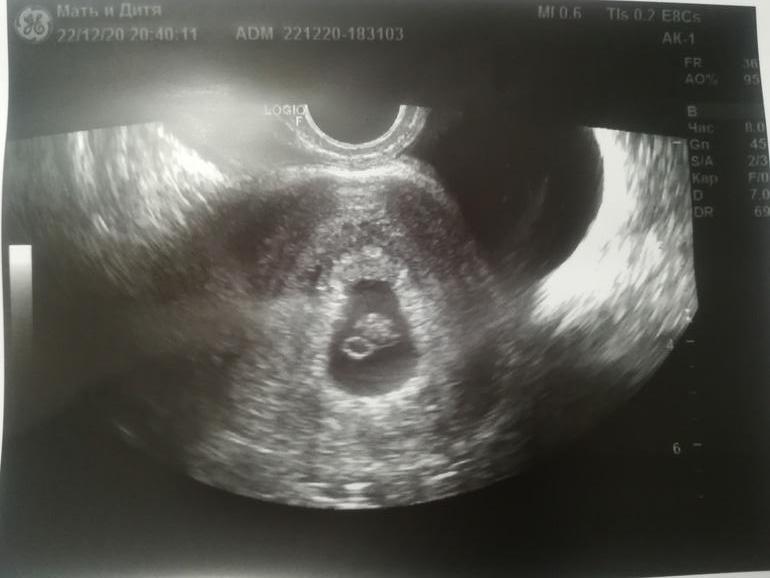

Моё самое любимое сердце в мире😍😍😍

Я БЕРЕМЕННА !Дорогие девочки, кто помнит меня и мои посты нытья по плохому росту ХГЧ(криоперенос 2-х пятидневок) . Нытьё отменяется🙊Сегодня на 32дпп я услышала сердце своего малыша, впервые в жизни в 33 года, я его услышала, это лучшее, что может быть в жизни😍😍😍Всё хорошо у нас, все по сроку, беременность по дате переноса 6.6 недели, по месячным 7.3,цикл был длинный и теперь эта неделя будет меня преследовать))) но это все не важно. С/Б+ ЧСС 125 уд/мин. Эмоций шквал, вместе с Ре плакали и умилялись, мы с ней прошли долгий пусть и это наша победа. Запомню этот день на всю жизнь. Самый лучший подарок в жизни. Чудеса случаются перед Новым годом, просто надо верить и я верю в своего малыша, в августе встретимся😍🤗Всем ждущим хгч, желаю чтобы он был трехзначный, всем ждущим узи, желаю услышать сердечки ваших малышей, всем лёгкой беременности и родов. Я СЧАСТЛИВА и хочется кричать об этом на весь мир🙊🙊🙊меняю кружок на желтенький.